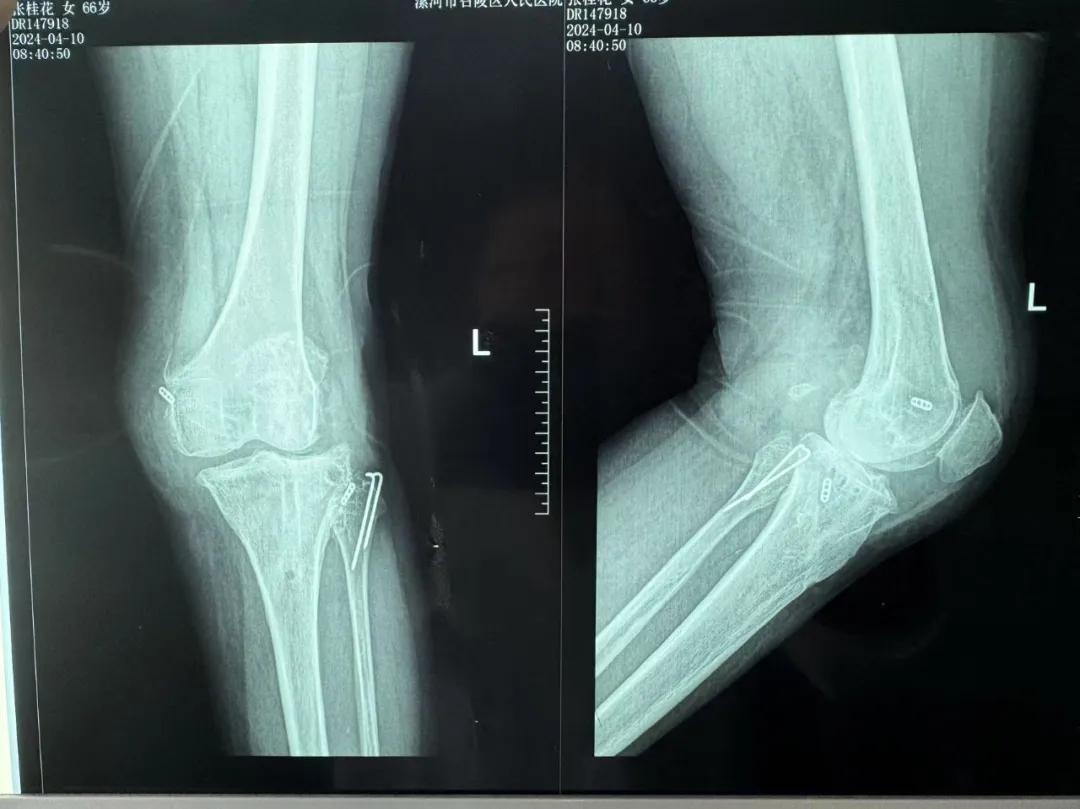

患者來(lái)院后,漯河市骨科醫(yī)院(漯河醫(yī)專二附院、漯河市立醫(yī)院)主治醫(yī)師康樂便成了她的管床醫(yī)生。在經(jīng)過詳細(xì)的術(shù)前診斷與檢查后,關(guān)節(jié)外科主任李付彬組織科室團(tuán)隊(duì)針對(duì)患者的診斷情況進(jìn)行術(shù)前討論——患者為重度膝關(guān)節(jié)骨關(guān)節(jié)炎,需進(jìn)行人工關(guān)節(jié)置換。但術(shù)前的評(píng)估結(jié)果顯示:患者膝關(guān)節(jié)側(cè)方不穩(wěn)定,單純行初次表面膝關(guān)節(jié)置換,術(shù)后仍會(huì)存在側(cè)方不穩(wěn)的情況,會(huì)影響術(shù)后效果以及假體使用年限,不僅無(wú)法完全恢復(fù)膝關(guān)節(jié)功能,還會(huì)加重患者的經(jīng)濟(jì)負(fù)擔(dān)。

為了盡可能給患者帶來(lái)更好的治療效果,減輕其經(jīng)濟(jì)負(fù)擔(dān),經(jīng)綜合評(píng)估后,李付彬主任帶領(lǐng)團(tuán)隊(duì)制定了最終的手術(shù)方案——決定使用髁限制性膝關(guān)節(jié)假體(LCCK)置換膝關(guān)節(jié)。作為解決患者病痛的最優(yōu)方案,這項(xiàng)手術(shù)具體實(shí)施的難度并不小,需要在術(shù)中根據(jù)截骨情況進(jìn)行多次評(píng)估和實(shí)時(shí)調(diào)整,這就要求主刀醫(yī)生不僅要具備過硬的專業(yè)技術(shù)與能力,還要能夠結(jié)合自身的經(jīng)驗(yàn)準(zhǔn)確判斷、精準(zhǔn)操作。

手術(shù)過程中,關(guān)節(jié)外科團(tuán)隊(duì)為患者進(jìn)行了標(biāo)準(zhǔn)截骨,經(jīng)過評(píng)估,患者膝關(guān)節(jié)仍存在膝關(guān)節(jié)側(cè)方不穩(wěn)定,便按照原定手術(shù)計(jì)劃使用LCCK假體進(jìn)行了膝關(guān)節(jié)置換。經(jīng)過再次評(píng)估,患者膝關(guān)節(jié)穩(wěn)定性恢復(fù),下肢力線正常,這臺(tái)高難度的LCCK膝關(guān)節(jié)置換手術(shù)在一小時(shí)內(nèi)便順利完成!術(shù)后第二天,患者就能夠自主下床負(fù)重活動(dòng),功能恢復(fù)良好。